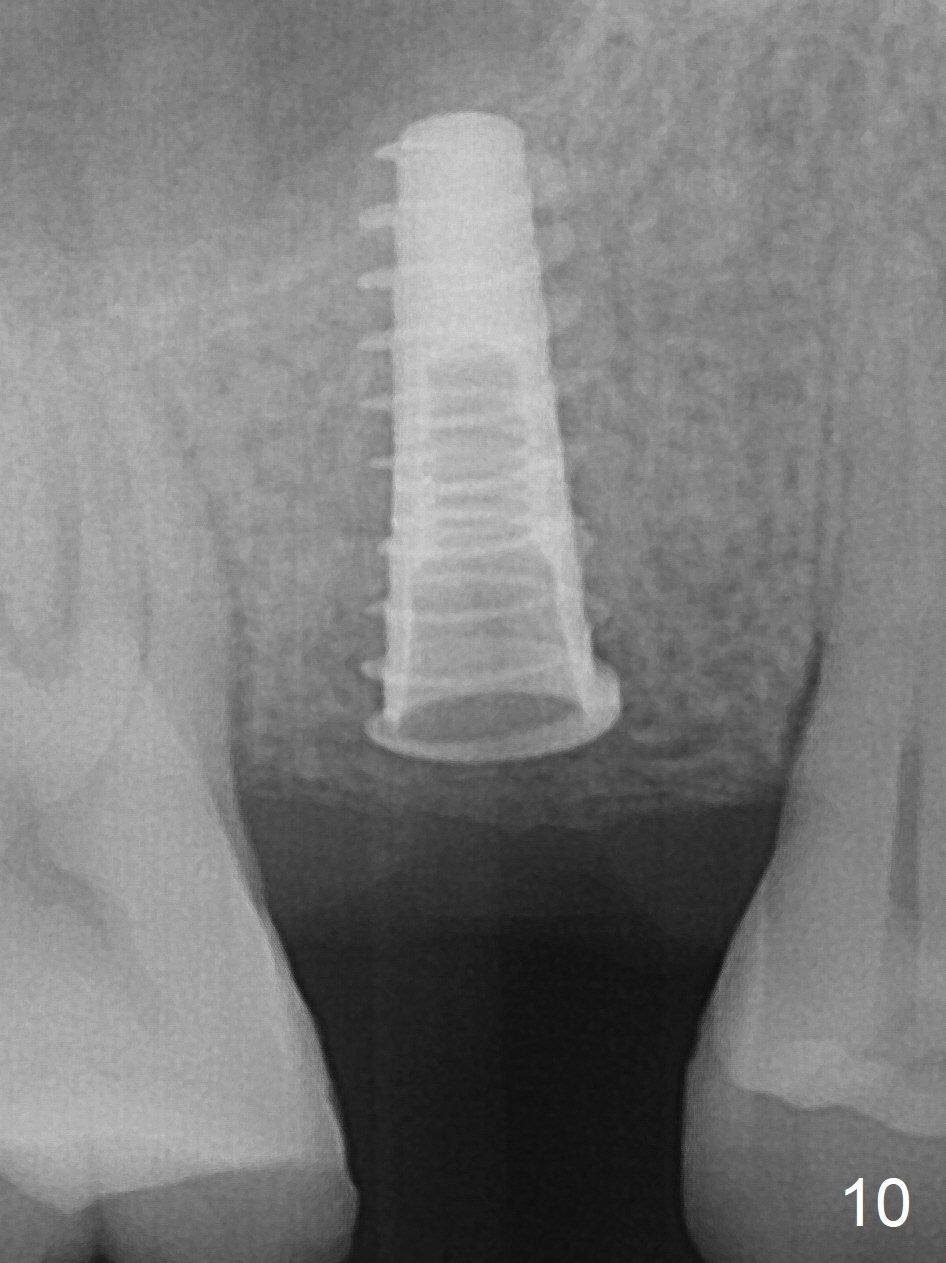

A 47-year-old man returns emergently with subgingival fracture of the lingual (L) cusp of the tooth #4 (Fig.1-3). After extraction (no bony defect) without drilling, a 4x11 mm dummy implant is placed as a tap drill with satisfactory stability (Fig.4,5). To get subcrestal placement, a shorter (4x9 mm) implant is inserted with insertion torque of < 35 Ncm. In retrospect, a larger implant (4.5 mm) would be better in term of primary stability. After allograft placement into the buccal and lingual gaps, a 4.5x4(4) mm abutment is placed for an immediate provisional. There is a peri-implant gap 7 months postop (Fig.7<, as compared to the implant at #2 (6 months postop)) . When the loose abutment is being retightened, the patient feels pain, although the gingiva appears healthy (Fig.8). A larger implant should have been used; the abutment should have been removed. The implant dislodges while the abutment is untightened 8 months postop. The osteotomy is found intact. A 4.5x11 mm dummy implant is placed 2 mm subgingival with 20 Ncm (Fig.9). When a 4.5x11 mm definitive implant is placed 3 mm subgingival (Fig.10,11), torque reaches 50 Ncm. A 5.5x3 mm healing abutment is placed. Three months postop, the implant is stable (Fig.12,13) and impression is taken.